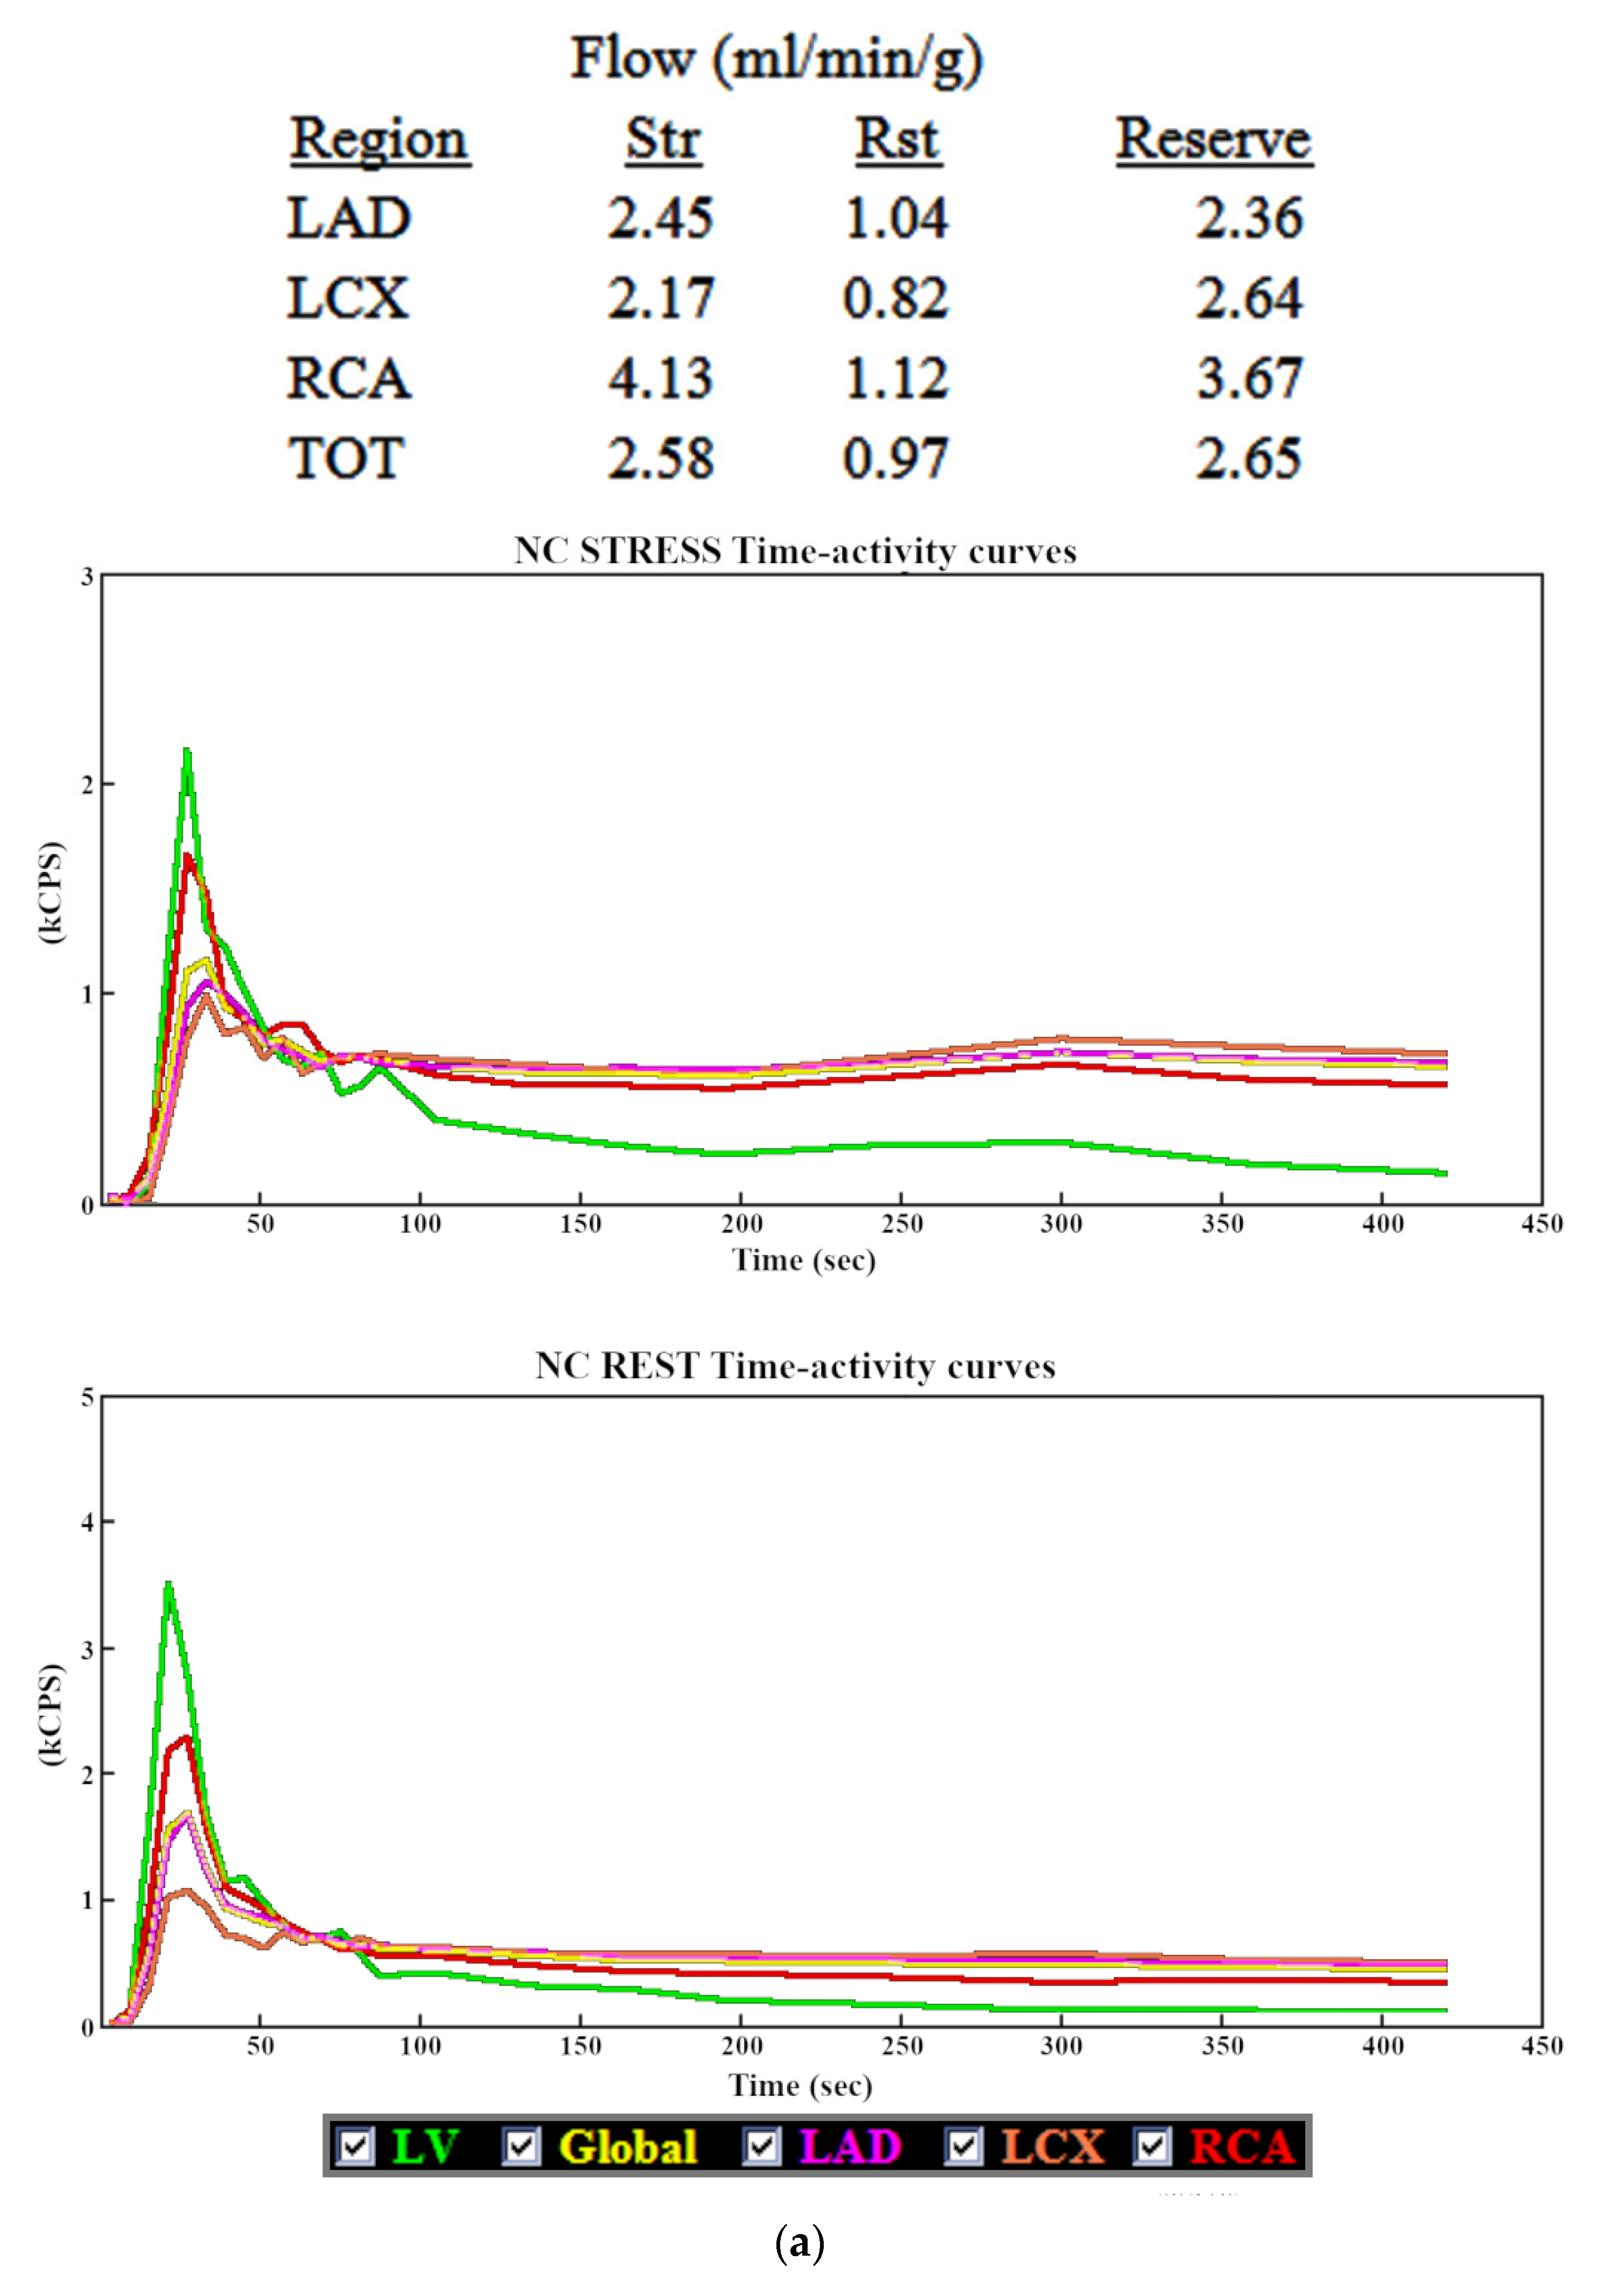

3.1. Myocardial Blood Flow

3.2. Myocardial Flow Reserve